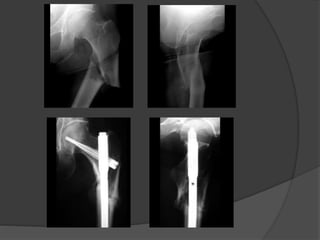

 Existen dos tipos de implante para estabilizar las fracturas

subtrocantéreas de fémur: (1) dispositivos de placa y

tornillo que se usan mediante reducción abierta y fijación

interna, y (2) clavos intramedulares aplicados mediante

técnicas abiertas o cerradas mínimamente invasivas

Tratamiento  Existendos tipos de implante para estabilizar las fracturas subtrocantéreas de fémur: (1) dispositivos de placa y tornillo que se usan mediante reducción abierta y fijación interna, y (2) clavos intramedulares aplicados mediante técnicas abiertas o cerradas mínimamente invasivas